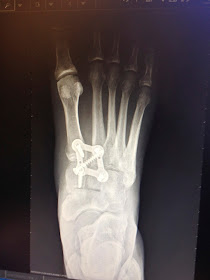

Wow!  Has this ever been a long journey!  But it some ways, it has also gone by quickly.  I cannot believe that today marks 11 weeks since my lisfranc surgery fracture repair!

11 Weeks post lisfranc surgery